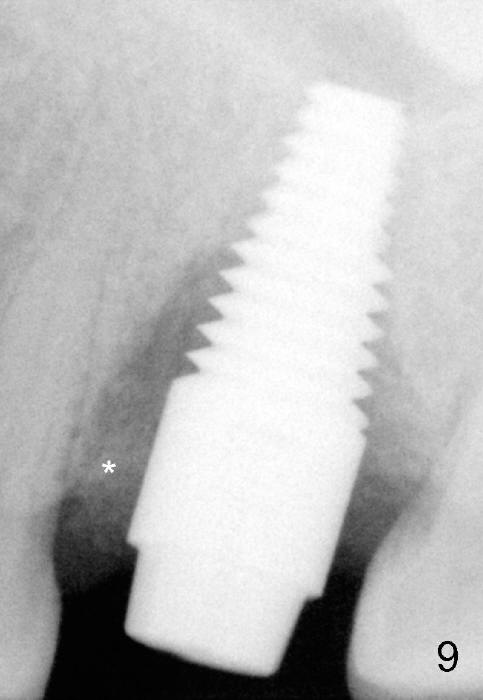

PA taken 3 months postop (Fig.9) shows bone graft in the mesial gap (*). Clinically the implant surface is less exposed buccally (Fig.10) than palatally (Fig.11 *).